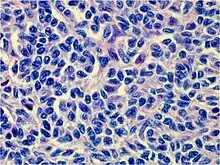

Histology

Juvenile granulosa cell tumors can be distinguished from adult granulosa cell tumors on histology by their abundant, eosinophilic cytoplasm; primitive, highly mitotic nuclei in polygonal cells; and disorganized follicles.[12][13]